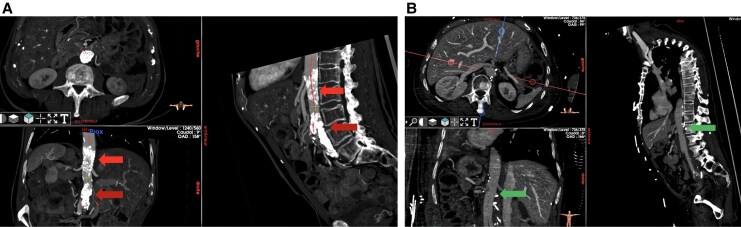

主动脉疾病,包括胸主动脉和腹主动脉的动脉瘤和闭塞性病变,是心血管发病率和死亡率的一个重要来源。本文探讨了现代和新兴的成像方式在主动脉疾病治疗中的作用,并强调了计算机断层血管造影(CTA)、磁共振成像(MRI)和超声造影(CEUS)的关键作用。CTA仍然是评估动脉瘤、夹层和创伤性损伤的基础,提供高空间分辨率、快速获取和详细的解剖评估。MRI,特别是先进的序列,如4D流,提供全面的多参数评估,而不需要辐射暴露,使其成为年轻患者和需要重复成像的理想选择。正电子发射断层扫描(PET),特别是当与CTA或MRI结合使用时,可以表征主动脉壁炎症和感染的代谢特征。超声,特别是超声造影,在腹主动脉瘤(AAA)筛查和血管内动脉瘤修复后(EVAR)监测中仍然是不可或缺的,特别是在肾功能损害患者中。包括混合成像、放射组学和人工智能(AI)在内的新兴技术正在重塑主动脉诊断的格局。这些创新增强了对细微成像特征的检测,自动化测量,并可能实现疾病进展或并发症的预测。

Aortic diseases, including aneurysmal and occlusive pathologies of the thoracic and abdominal aorta, represent a significant source of cardiovascular morbidity and mortality. This narrative review explores the role of modern and emerging imaging modalities in the management of aortic disease and highlights the pivotal roles of computed tomography angiography (CTA), magnetic resonance imaging (MRI), and contrast-enhanced ultrasound (CEUS). CTA remains the cornerstone for evaluating aneurysms, dissections, and traumatic injuries, offering high spatial resolution, rapid acquisition, and detailed anatomical assessment. MRI, particularly with advanced sequences such as 4D flow, provides comprehensive multiparametric evaluation without radiation exposure, making it ideal for younger patients and those requiring repeat imaging. Positron emission tomography (PET), especially when integrated with CTA or MRI, enables metabolic characterization of inflammation and infection in aortic walls. Ultrasound, particularly CEUS, remains indispensable in abdominal aortic aneurysm (AAA) screening and post-endovascular aortic aneurysm repair (EVAR) surveillance, especially in patients with renal impairment. Emerging technologies, including hybrid imaging, radiomics, and artificial intelligence (AI) are reshaping the landscape of aortic diagnostics. These innovations enhance detection of subtle imaging features, automate measurements, and may enable prediction of disease progression or complications.